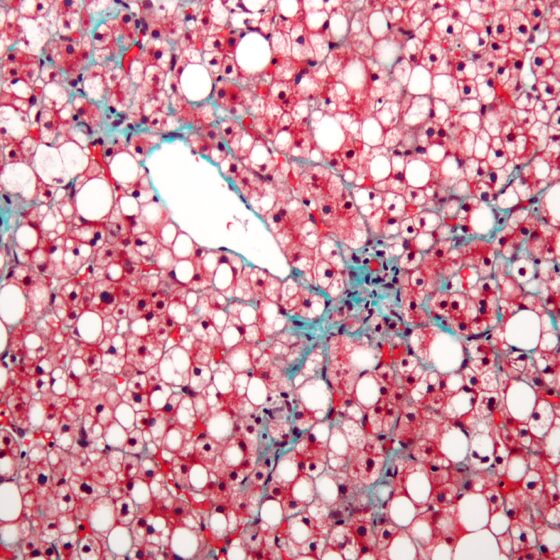

• Lebersteatose bei metabolischer Dysfunktion

Neue Nomenklatur für die nicht-alkoholische Fettlebererkrankung

Der Begriff «nicht-alkoholische Steatohepatitis» (NASH) wurde ursprünglich verwendet, um eine Leberschädigung zu beschreiben, die durch lobuläre Entzündung, Steatose und Ballonierung von Hepatozyten gekennzeichnet ist. Zudem wurde damals ein grosser Teil...…

• Vom Symptom zur Diagnose

Abdominalschmerz – Steatosis hepatis

Bei steatotischen Lebererkrankungen werden unter ätiologischen Gesichtspunkten die nichtalkoholische Fettlebererkrankung (NAFLD) bzw. nichtalkoholische Steatohepatitis (NASH) von der alkoholischen Fettleber (AFLD) bzw. alkoholischen Steatohepatitis (ASH) unterschieden. Ausmass der Verfettung und Entzündungsgrad...…